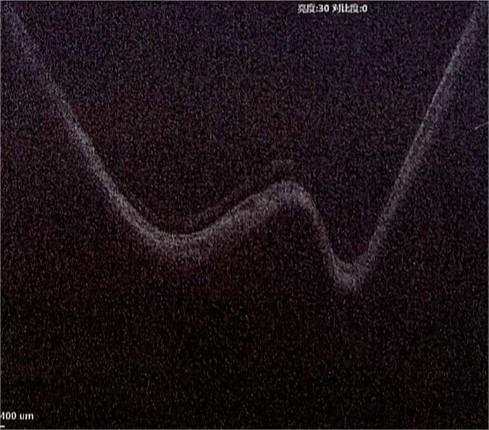

患者术后第一天OCT,视网膜劈裂消失,裂孔闭合

术后第二天,患者的黄斑劈裂就基本消失,较内路玻璃体切割手术术后恢复时间大大缩短,为患者带来了更好的治疗和康复效果。